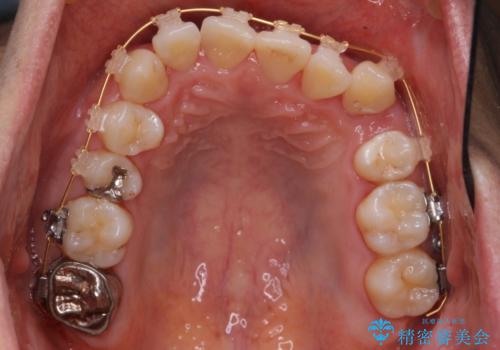

- 矯正装置

- 審美装置

- 受け口を主訴に来院。

下あごが大きく、顎の手術を含めた矯正をおすすめしましたが、手術は怖いので絶対にしたくないとのことでした。

歯並びのみを治す矯正は難しく、長期にわたる治療になるとご説明しました。

かみしめもあり、骨も固く、歯根も長いためなかなか歯が動かず、患者様も治療する側も忍耐を要する長期戦となりました。